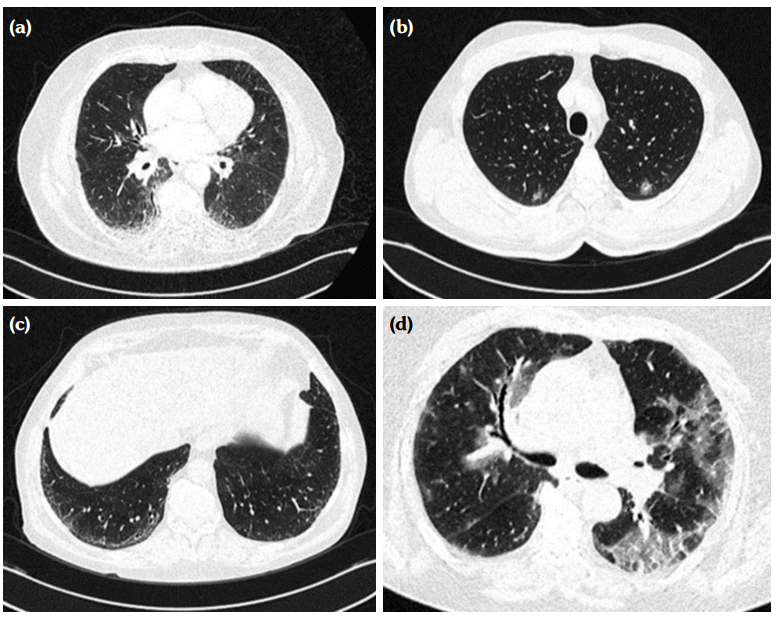

Thoracic CT and HRCT findings were as follows: ground glass opacity in 10 (40%), geographic pattern in four (16%), traction bronchiectasis in three (12%), interlobular septal thickening in three (12%), reticular pattern in three, (12%) and pulmonary arterial hypertension in two (8%) patients. Honeycombing was present in none of the subjects (Figure 1).

Among the nine patients with ILD, the most common patterns recognized were nonspecific interstitial pneumonia (NSIP) in three (1.2%), cryptogenic organizing pneumonia in two (0.8%), probable usual interstitial pneumonia (UIP) in two (0.8%), and unclassified type in two (0.8%) patients (Table 3). Figure 2 presents some examples for pulmonary involvement patterns. Mean values for FVC (forced vital capacity), FEV1 (forced expiratory volume in 1 sec), and FEV1/FVC of these patients were 67.4±30.6, 74.0±38.8, and 74.1±30.4, respectively.